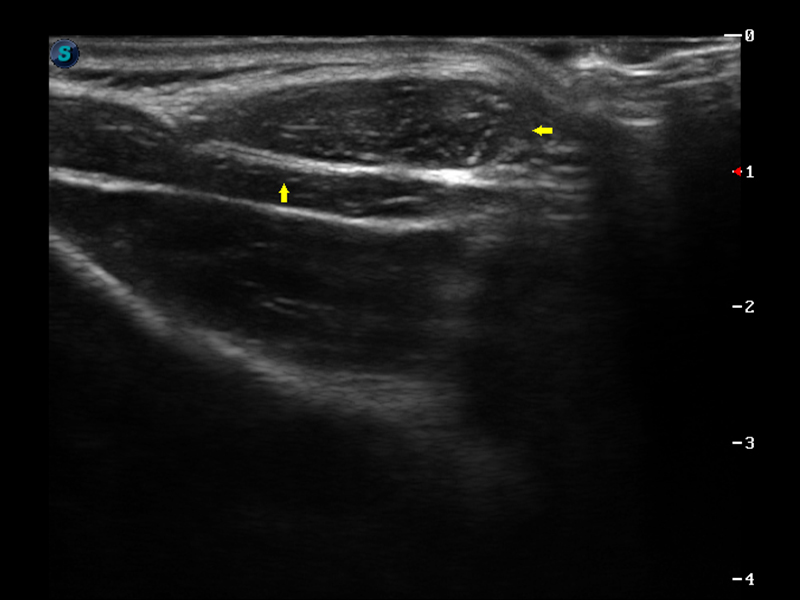

S9便携式彩色多普勒超声诊断仪是16877太阳集团研发的高端便携彩超设备,外观设计新颖、产品性能卓越。S9在便携超声领域采用了突破传统的触摸屏交互设计,并以先进的软件硬件技术和设计理念,为您带来清晰的图像质量、稳定的工作性能和便捷的操作体验。